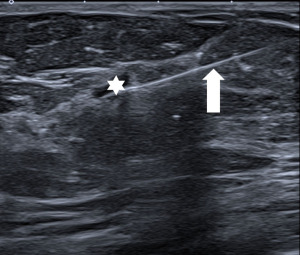

Ultrasound of the axilla (axillary ultrasound) is mandatory for staging of the disease. Various features of lymph nodes are considered suspicious of metastatic involvement: cortical thickening of more than 3mm, irregular cortex width, displacement or absence of the fatty hilum or round shape of the lymph node (Figure 5). Ultrasound is also the method used to navigate the fine needle aspiration biopsy (FNA/FNAB) to confirm the status of the lymph node (34), with high sensitivity (79.6%), specificity (98.3%) and PPV 97.1% for identification of axillary involvement. With decreasing radicality of axillary surgery, the main advantage of axillary ultrasound is its ability to reliably identify or exclude a major axillary tumour burden (35).